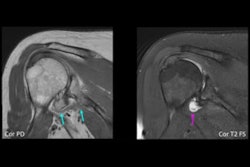

The study included 105 patients who underwent 110 MRI exams. The investigators compared standard shoulder MRI sequences (9 minutes) and accelerated ones (3 minutes) for image quality and diagnostic performance; all patients had both. Standard sequences were reconstructed with conventional techniques, while the accelerated sequences were reconstructed with a conventional technique alone and with a conventional technique plus a deep learning algorithm (AIR Recon DL, GE Healthcare).

Two radiologists evaluated the MRI images for image quality and clarity using a four-point scale (with 1 representing poor and 4 indicating excellent). They also assessed images for artifacts using a four-point scale (with 1 meaning severe artifacts and 4 signifying no artifacts). Scores for each of three imaged planes were added for a total score of 3 to 12 for both image quality and artifacts.

The accelerated MRI shoulder exam sequences were accomplished in 67% less scan time, although they did have poorer image quality and artifacts compared with the standard sequences. But using the deep learning-based reconstruction helped, however.